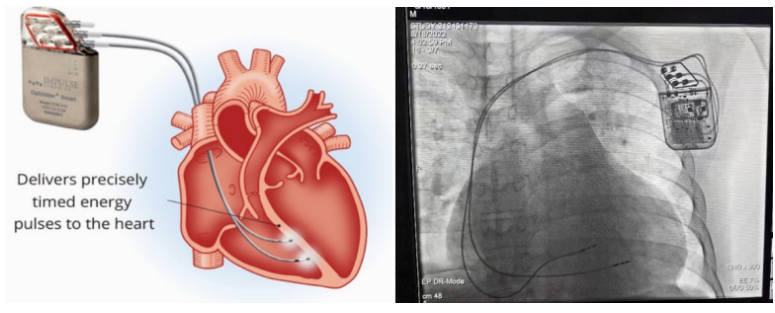

①植入式心臟復(fù)律除顫器

Implantable Cardioverter Defibrillator,ICD

植入式心臟復(fù)律除顫器是一種具有除顫功能的高級(jí)起搏器,是一種體積小、能植入患者胸部皮下組織的醫(yī)療設(shè)備。慢性心衰患者易發(fā)生室性心動(dòng)過(guò)速或心室顫動(dòng),導(dǎo)致心源性猝死(SCD)。ICD 則能在幾秒內(nèi)自動(dòng)識(shí)別并治療快速室性心律失常,通過(guò)低能量心臟轉(zhuǎn)復(fù)和高能量除顫等功能,顯著降低惡性室性心律失常引起的猝死風(fēng)險(xiǎn)??杉皶r(shí)自動(dòng)為患者轉(zhuǎn)復(fù)心律,通俗地說(shuō)就是裝在體內(nèi)的自動(dòng)除顫儀。

國(guó)內(nèi)研發(fā)企業(yè):無(wú)雙醫(yī)療、邁瑞、魚(yú)躍、久心、微創(chuàng)、維偉思、麥邦等

②心臟再同步治療

Cardiac Resynchronization Therapy,CRT

心臟再同步化治療,指雙心室起搏器,是通過(guò)雙心室同步起搏的方式,幫助心衰患者實(shí)現(xiàn)正常起搏的裝置。CRT包括一個(gè)口袋大小的脈沖發(fā)生器和三根電極導(dǎo)線(xiàn),可被植入人體。通過(guò)監(jiān)測(cè)心律,在發(fā)現(xiàn)異常后,信號(hào)發(fā)生器發(fā)送電流脈沖,刺激心室重新同步,從而改善癥狀,提高患者的心臟泵血效率。目前有兩種類(lèi)型的CRT裝置:植入式心臟再同步治療起搏器(CRT-P)和植入式心臟再同步治療除顫器(CRT-D)。主要區(qū)別在于后者除了改善心臟收縮同步性外,還具備除顫功能,能及時(shí)處理危及生命的室性心律失常,避免猝死。

國(guó)內(nèi)研發(fā)企業(yè):無(wú)雙醫(yī)療、樂(lè)普醫(yī)療、先健科技、創(chuàng)領(lǐng)心律、秦明醫(yī)學(xué)等